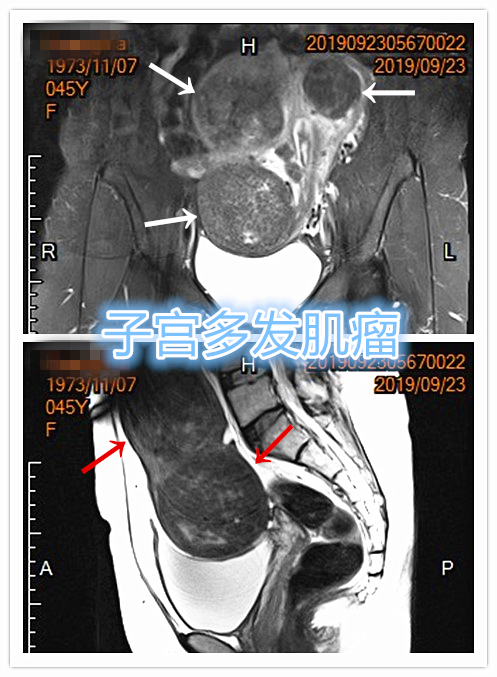

中年女性,发现子宫肌瘤进行性增大5年余。复查彩超提示多发肌瘤,较前明显增大(最大者直径近10cm)。近半年尿频、尿急症状进行性加重,考虑增大的子宫肌瘤压迫膀胱所致。

- 盆腔磁共振检查显示显示多发子巨大宫肌瘤,压迫膀胱

MRI显示多发子巨大宫肌瘤,压迫膀胱

MRI显示子宫多发巨大肌瘤